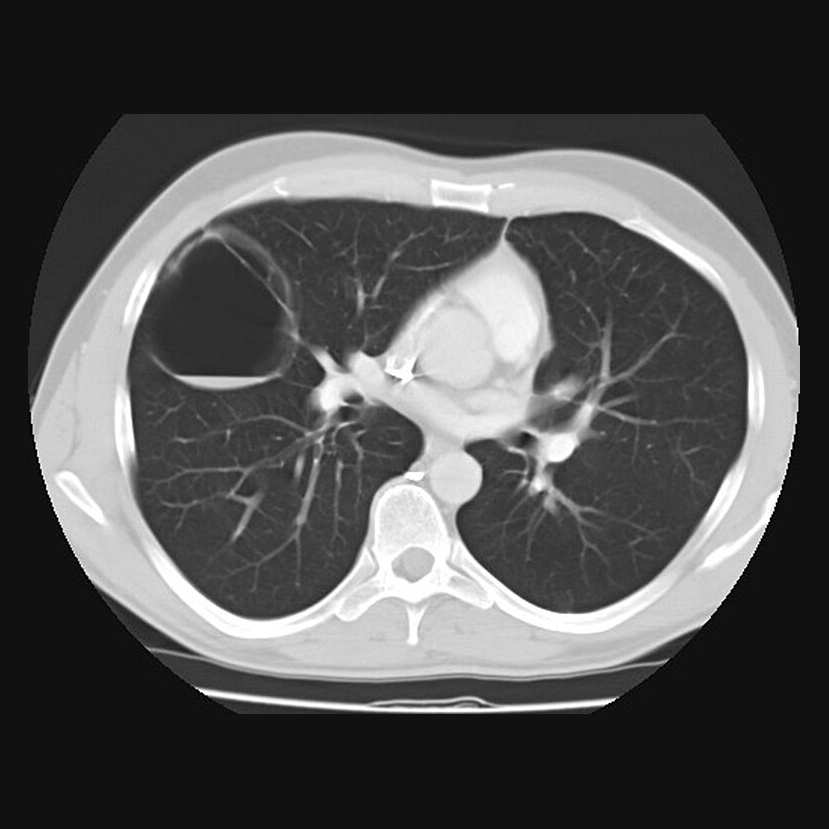

A chest CT scan (computed tomography scan) is a painless, non-invasive imaging test that gives doctors detailed pictures of your child’s chest, including the lungs, heart, airways, blood vessels, lymph nodes, and bones. CT scans use special X-ray technology to take multiple images from different angles and combine them into cross-sectional views. These scans can provide more information than a standard chest X-ray.